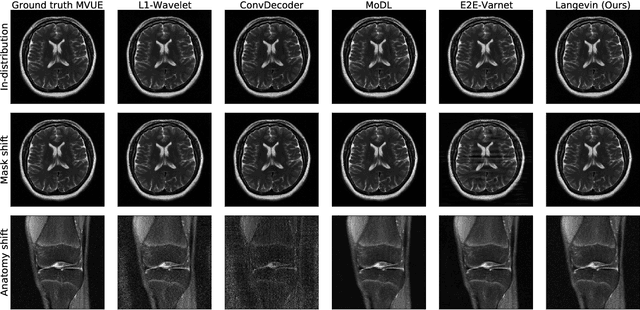

The CSGM framework (Bora-Jalal-Price-Dimakis'17) has shown that deep generative priors can be powerful tools for solving inverse problems. However, to date this framework has been empirically successful only on certain datasets (for example, human faces and MNIST digits), and it is known to perform poorly on out-of-distribution samples. In this paper, we present the first successful application of the CSGM framework on clinical MRI data. We train a generative prior on brain scans from the fastMRI dataset, and show that posterior sampling via Langevin dynamics achieves high quality reconstructions. Furthermore, our experiments and theory show that posterior sampling is robust to changes in the ground-truth distribution and measurement process. Our code and models are available at: \url{https://github.com/utcsilab/csgm-mri-langevin}.